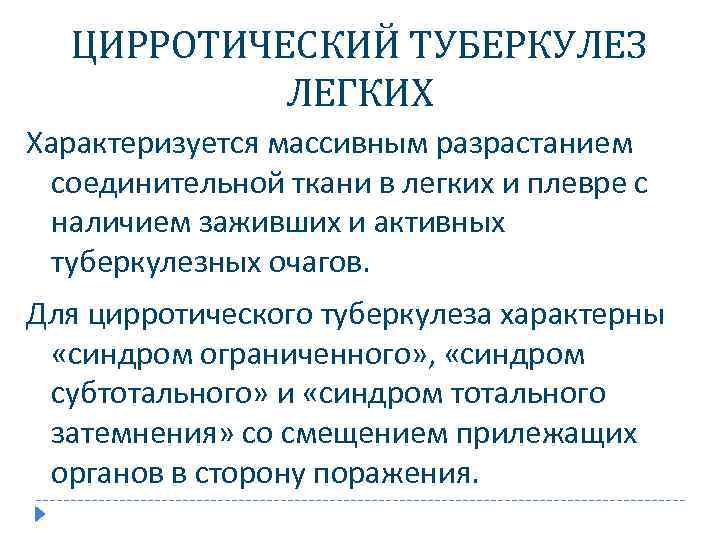

ЦИРРОТИЧЕСКИЙ ТУБЕРКУЛЕЗ ЛЕГКИХ Характеризуется массивным разрастанием соединительной ткани в легких и плевре с наличием заживших и активных туберкулезных очагов. Для цирротического туберкулеза характерны «синдром ограниченного» , «синдром субтотального» и «синдром тотального затемнения» со смещением прилежащих органов в сторону поражения.

ЦИРРОТИЧЕСКИЙ ТУБЕРКУЛЕЗ ЛЕГКИХ Характеризуется массивным разрастанием соединительной ткани в легких и плевре с наличием заживших и активных туберкулезных очагов. Для цирротического туберкулеза характерны «синдром ограниченного» , «синдром субтотального» и «синдром тотального затемнения» со смещением прилежащих органов в сторону поражения.